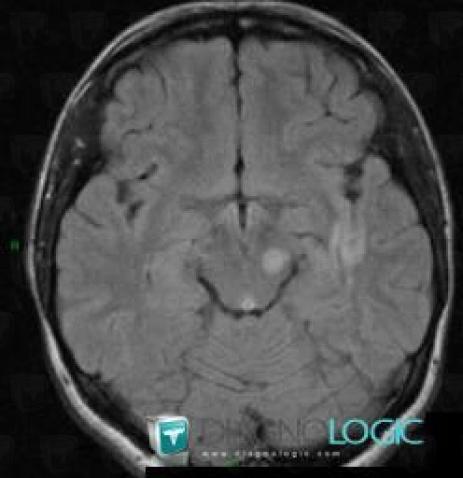

Multiple sclerosis, Cerebral hemispheres, MRI

Here is the specific information in the key image above:

- Diagnosis Multiple sclerosis, Location(s) Cerebral hemispheres, with gamuts Intracerebral T2W or FLAIR hyperintense lesion, White matter disease, Multifocal intracranial lesions